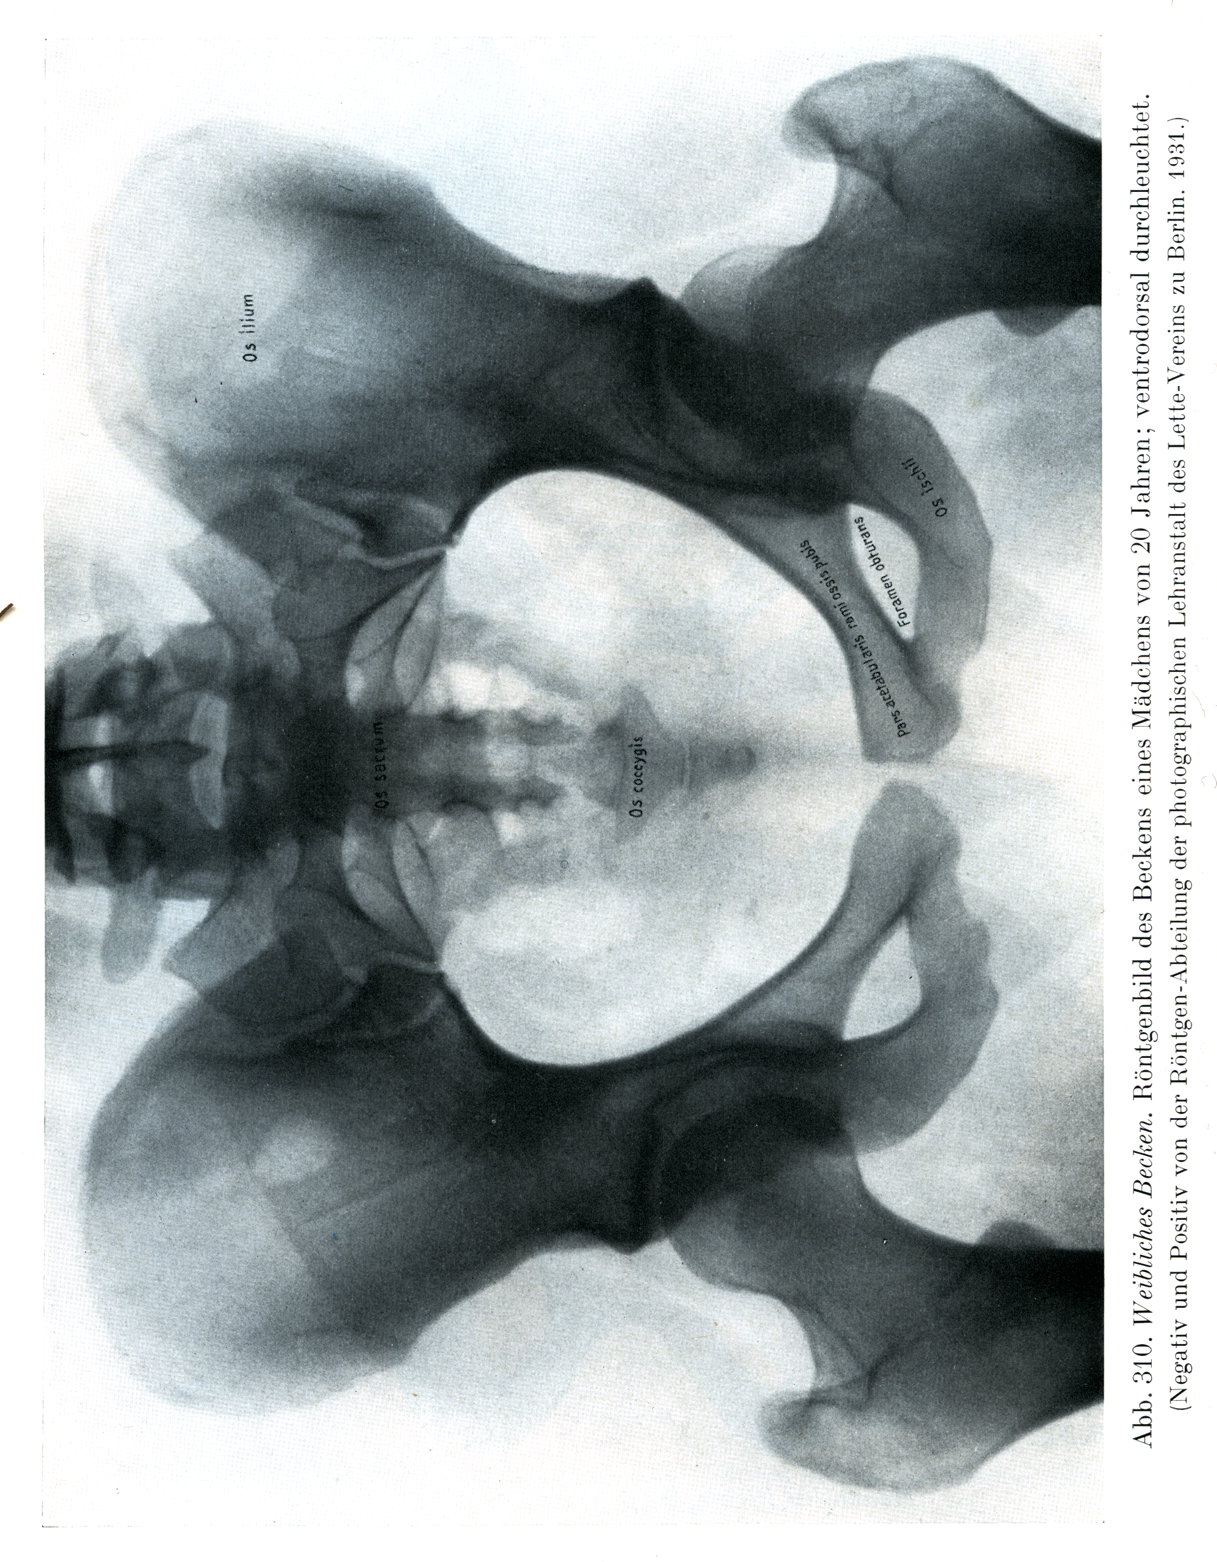

[図310]

女の骨盤

20才の少女の骨盤のレントゲン写真, 腹背照射.